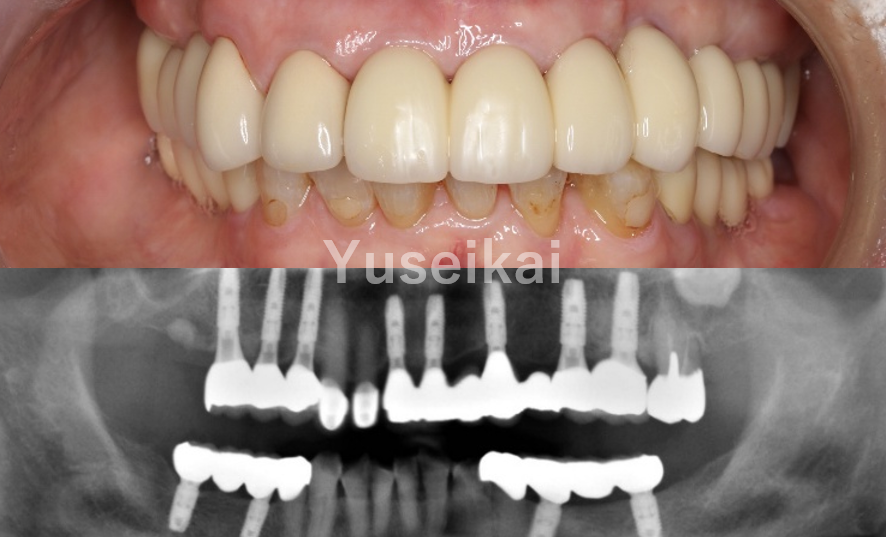

多くの歯を失ってしまった場合、歯の再建を行うことで、全体の噛み合わせや美しい口元を取り戻すことが重要です。当院では、歯を失ってしまった症例ごとに状態を綿密に把握し、適切な治療計画をご提案いたします。

ボーンアンカードブリッジ

インプラントをアンカーとして、顎の骨にブリッジをしっかりと固定する治療法です。取り外しの必要がなく、天然歯と同じような感覚で力強く噛むことができます。見た目も自然で安定性に優れており、ズレや脱落の心配がない固定式の人工歯です。

オールオン4・6・8

オールオン4・6・8は、4本、6本または8本のインプラントを埋入し、上下どちらかの前歯から奥歯までの人工歯を固定する治療法です。安定性が良好なため外れにくく、自然な見た目で審美性にも優れています。総入れ歯にお悩みの方は、ぜひご相談ください。